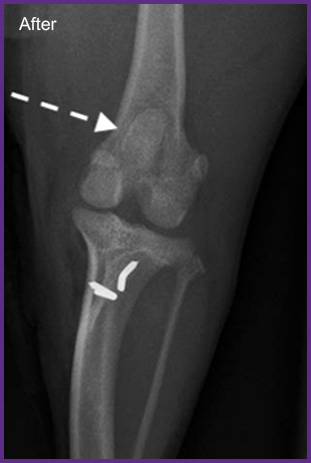

我們提供留院服務並擁有相應的治療設施,亦是小數備有CT電腦掃描及MRI磁力共振等大型醫療儀器的診所及醫院。